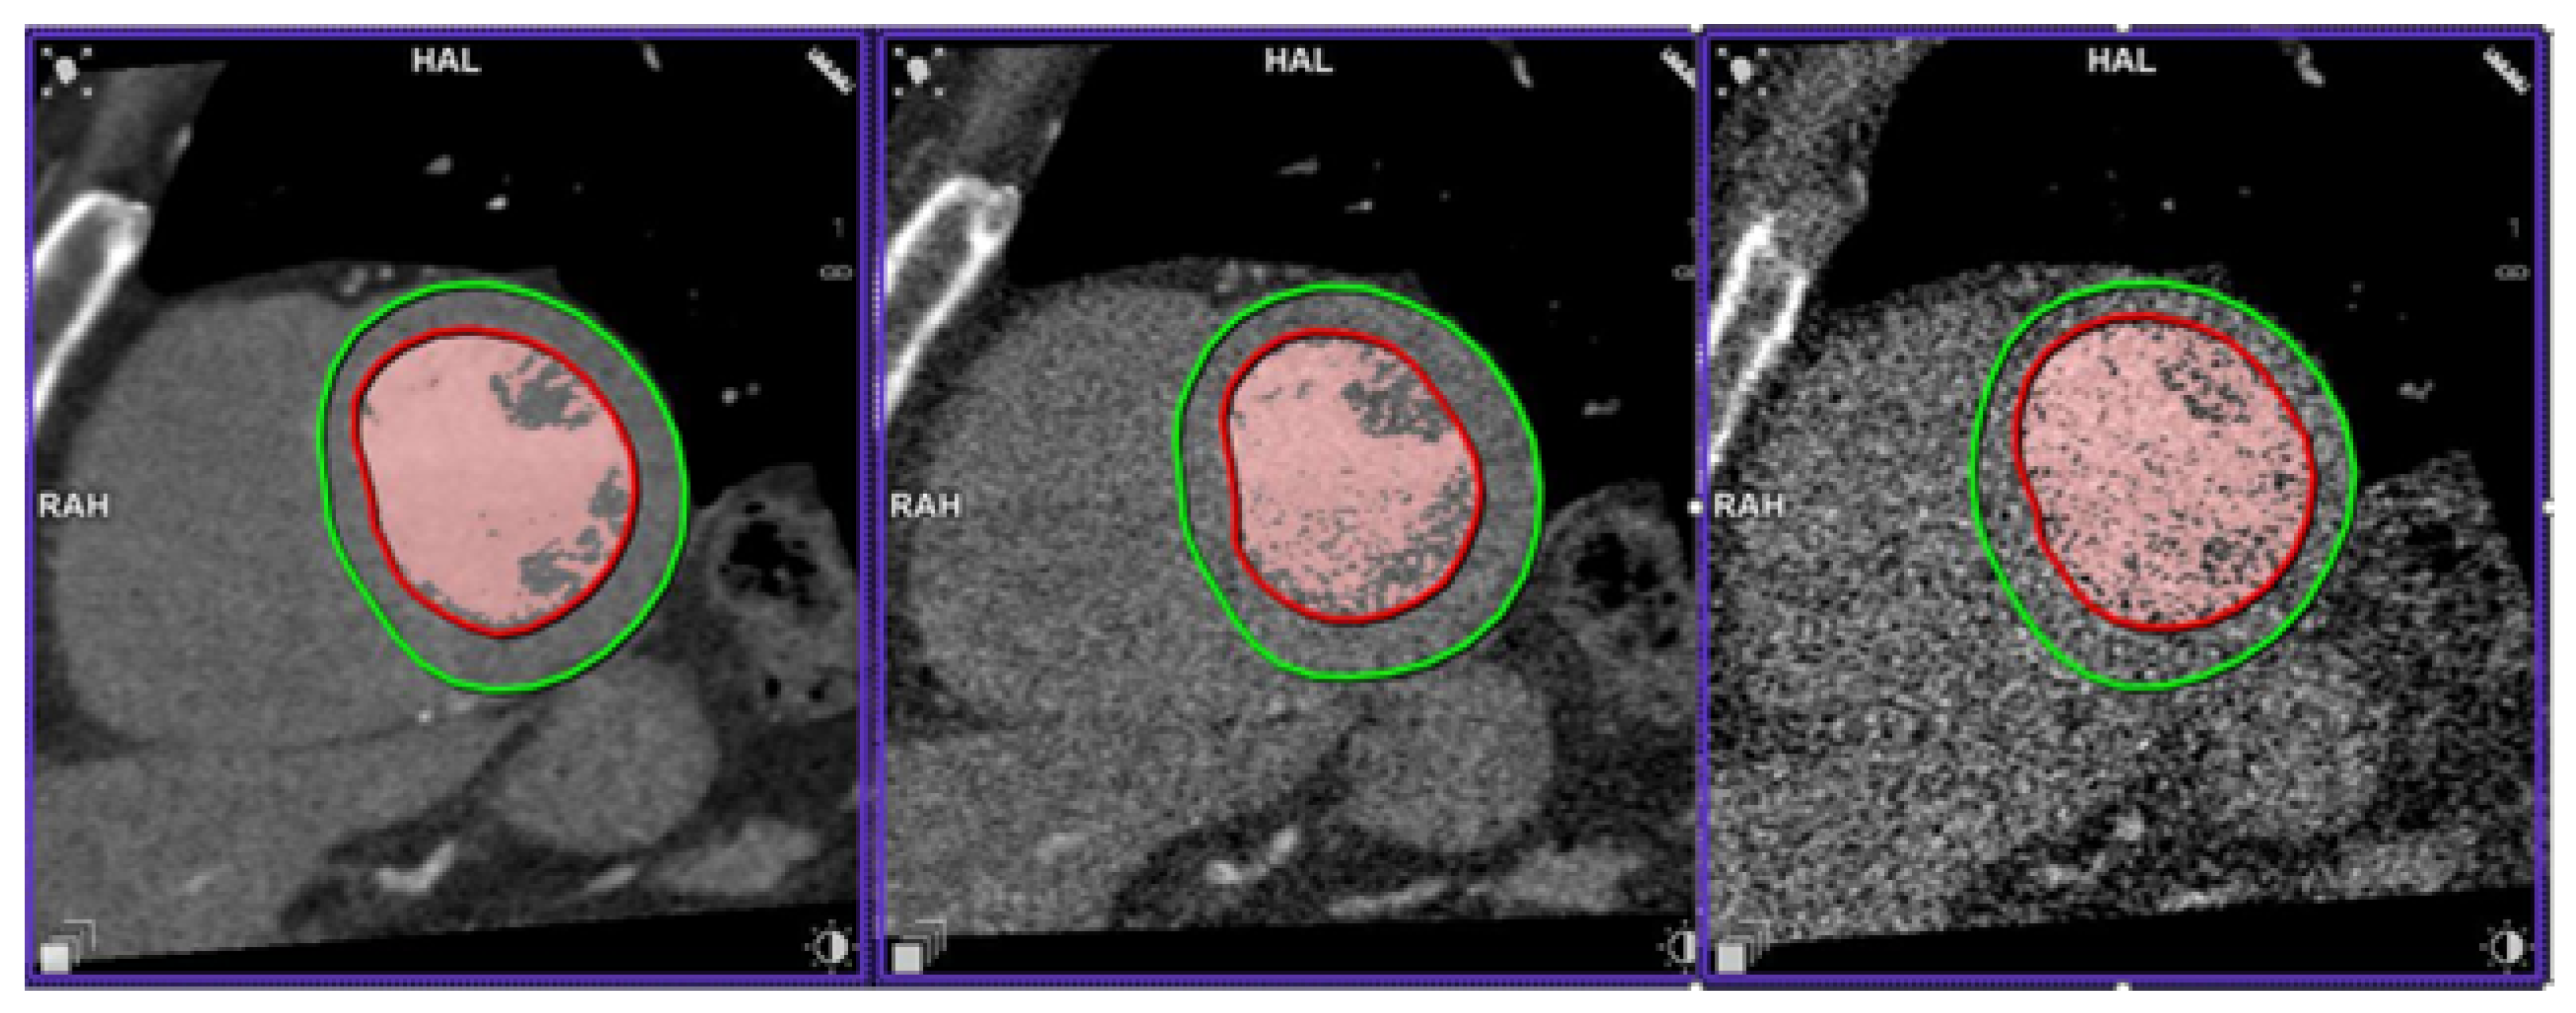

An example of a study simulated at the five dose levels can be seen in Figure 5 and a study with Syngo.Via volume measurement at three dose levels is presented in Figure 6.

Figure 6. Left ventricle segmentation at 100, 10 and 2% of the initial dose. The red contours are the automatic LV endocardium segmentation. Red-coloured pixels are those above the threshold for LV volume calculation in blood volume mode. The green countours are LV epicardium segmentation, not used in LVEF calculation.